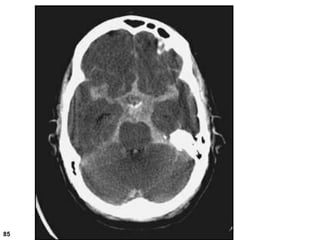

Sphenoid

sinus

Medulla

oblongata

cerebellum

4 Fourth ventricle

5 Middle cerebellar

peduncle

6 Sigmoid sinus

7 Petrous temporal

bone and mastoid

air cells

8 Cerebellopontine

angle

9 Pons

10 Pituitary fossa

11 Cerebellar

vermis

12 Basilar artery

13 Prepontine

cistern

14 Dorsum sellae

15 Temporal horn

of lateral

ventricle

16 Ambient

17

Interpeduncular

18 Cerebral

19 Sylvian

fissure

20 Supra

vermian

21 Frontal

horn of

lateral

21a Third

22 Head of

caudate

nucleus

23 Insular

cortex

24 External

capsule

25 Lentiform

26 Thalamus

27 Interhemispheric

28 Anterior limb of

internal capsule

29 Genu of internal

30 Posterior limb of

31 Trigone of lateral

ventricle and calcified

choroid plexus

32 Occipital horn of

lateral ventricle